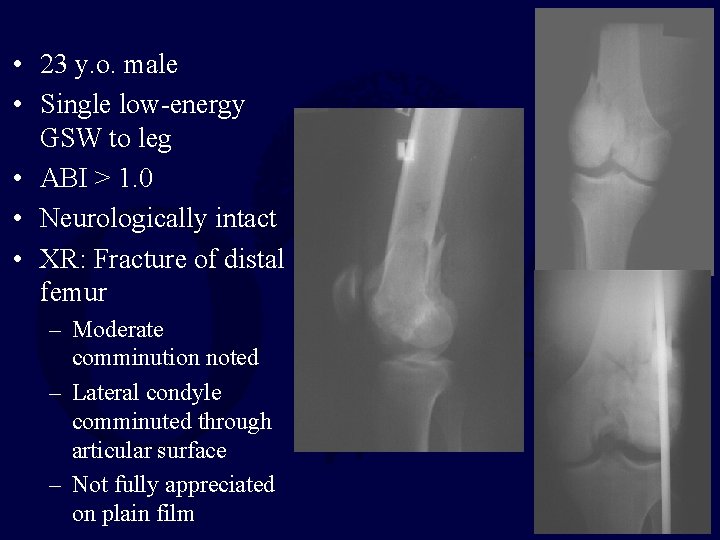

• 23 y. o. male • Single low-energy GSW to leg • ABI > 1. 0 • Neurologically intact • XR: Fracture of distal femur – Moderate comminution noted – Lateral condyle comminuted through articular surface – Not fully appreciated on plain film

Note fixation of lateral condyle for unappreciated comminution